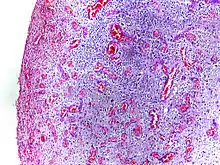

Morphologic patterns

Specific patterns of acute and chronic inflammation are seen during particular situations that arise in the body, such as when inflammation occurs on an epithelial surface, or pyogenic bacteria are involved.

- Fibrinous inflammation: Inflammation resulting in a large increase in vascular permeability allows fibrin to pass through the blood vessels. If an appropriate procoagulative stimulus is present, such as cancer cells,[10] a fibrinous exudate is deposited. This is commonly seen in serous cavities, where the conversion of fibrinous exudate into a scar can occur between serous membranes, limiting their function. The deposit sometimes forms a pseudomembrane sheet. During inflammation of the intestine (Pseudomembranous colitis), pseudomembranous tubes can be formed.

- Purulent inflammation: Inflammation resulting in large amount of pus, which consists of neutrophils, dead cells, and fluid. Infection by pyogenic bacteria such as staphylococci is characteristic of this kind of inflammation. Large, localised collections of pus enclosed by surrounding tissues are called abscesses.